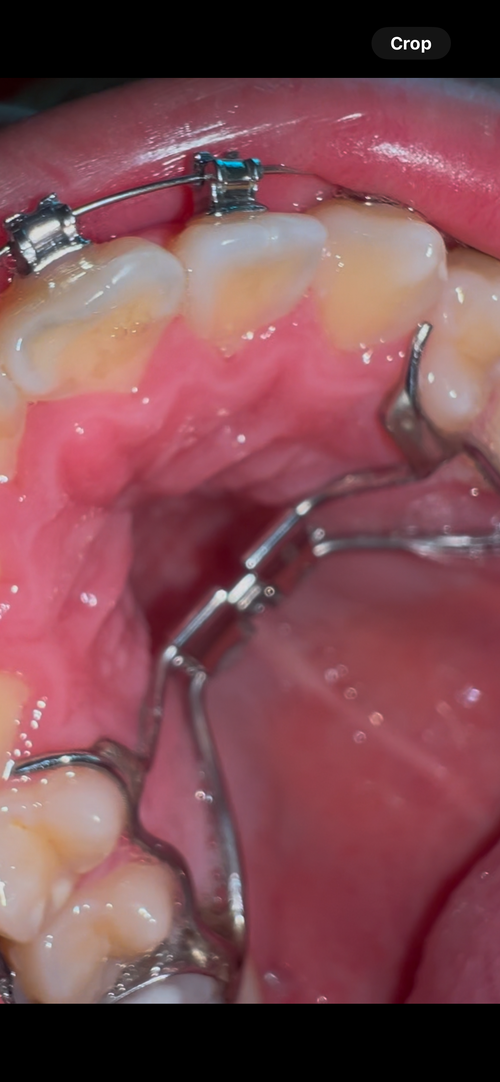

ltn-htn via double jaw surgery dowgrafting + ccw